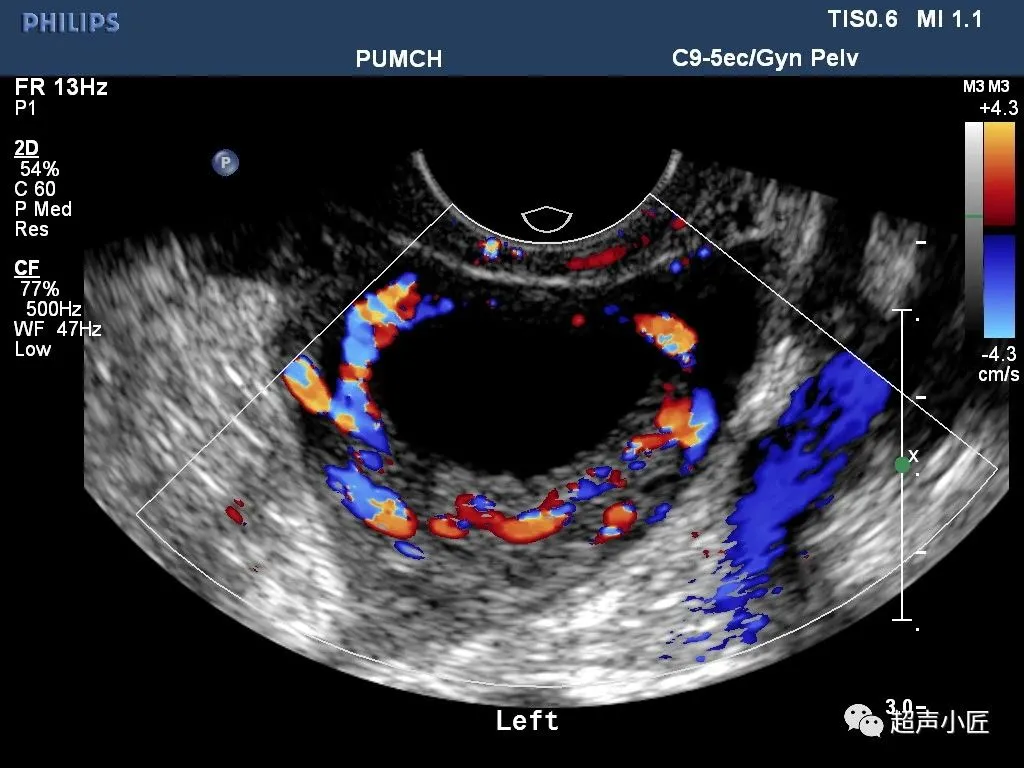

浆液性囊腺癌

●是临床上最常见的卵巢恶性肿瘤,约占卵巢恶性肿瘤的40%-60%,半数为双侧,乳头可穿过瘤壁向外生长。

●二维超声图特征:呈圆形或椭圆形,表面光滑或不规则;囊壁厚;多显示囊实性,囊液清亮或混浊,内壁有毛刷状小乳头,强回声粗大乳头,实质部分呈强回声或低回声;血流较丰富;多伴有腹水。